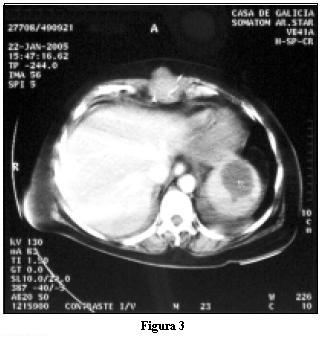

Al 11º día síndrome febril con episodio de bacteriemia que provoca caída de la diuresis y reinstalación de inotrópicos. Ronda bacteriológica negativa, ETE s/p, TAC de cráneo s/p y TAC abdominopélvica que objetiva imagen esplénica polar superior compatible con absceso de 45 mm de diámetro. FIGURA 3

Desde el punto de vista imagenológico es de elección ante su sospecha la realización de TAC, que distingue entre infarto y absceso con una especificidad y sensibilidad de 95 y 92% respectivamente.(13)